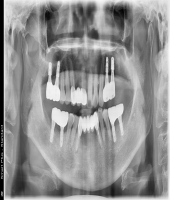

| ● 진료과목 : [임플란트] 임플란트 지지 틀니

| ● 내용 : 상악 임플란트 지지 틀니와 하악 고정식 보철의 만남. |